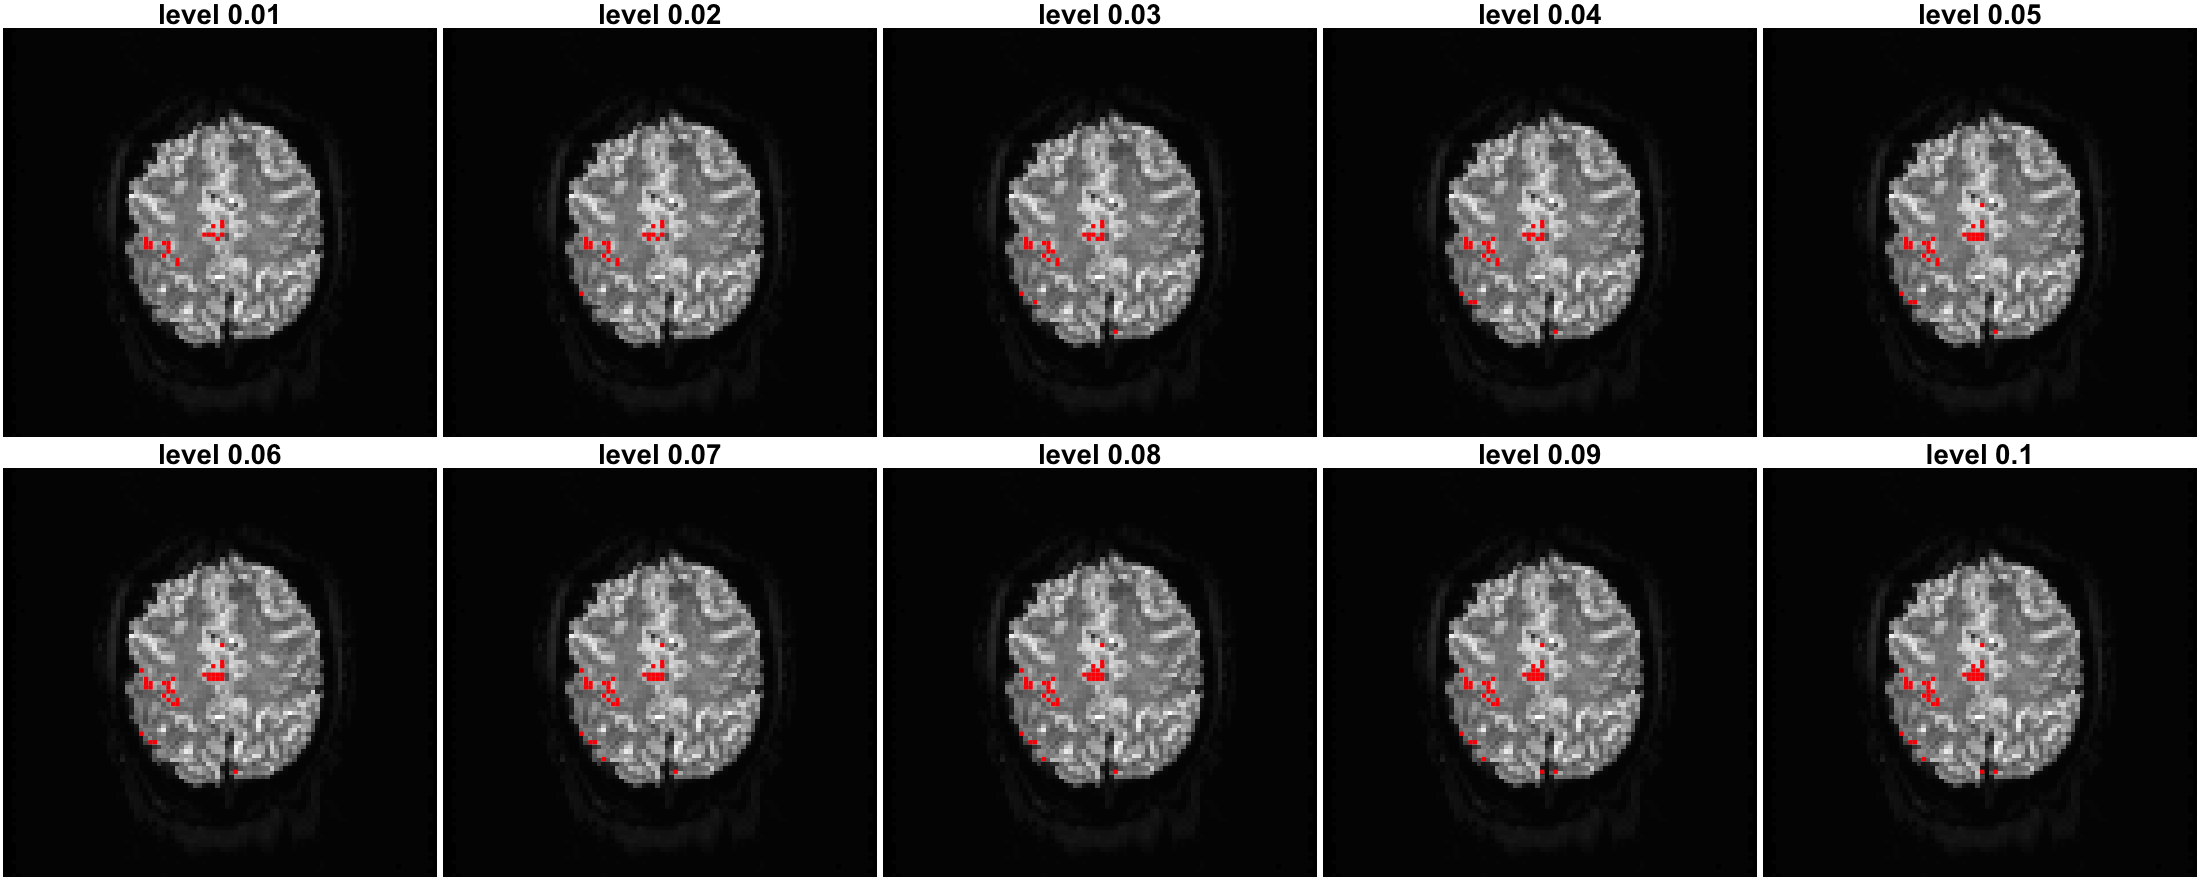

Activation is viewed as variable selection and done by inclusion of zero of credible intervals.

The strength of M-Cplx is measured by \sqrt{\beta_{re}^2 + \beta_{im}^2} \in (0, \infty) and that of M-Mag is the \beta from the real-valued model.

CV-GDP

CV-Bayesian Lasso

MO-GDP

MO-Bayesian Lasso

Either complex or real-valued, GDP shrinks coefficients more when their intensity is small.

Strength by MO models is weaker.

The NON-spatial NON-temporal CV models could perform as good as sophisticated spatiotemporal real-valued MO models (Yu et al., 2018, 2023).

We are working on selecting the best activation via information criteria such as WAIC and DIC.

One credible level cannot serve for all data and prior types.